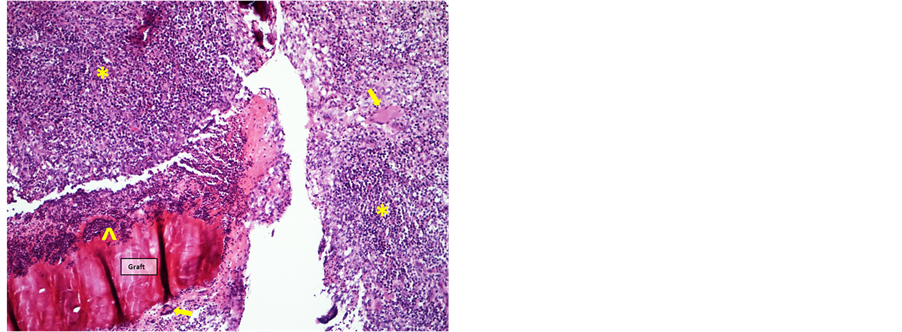

Two weeks postoperatively, the graft site showed extensive neutrophilic inflammation enclosing and infiltrating the fish skin graft, with a surrounding layer of mononuclear leukocytes and a few multinuclear giant cells. The subarachnoid space was closed by infiltration of lymphocytes and macrophages. (Figure 7 and Figure 8)

Figure 7. Graft 2 weeks postoperatively infiltrated by neutrophils (^) and surrounded by a layer of mononuclear leukocytes (*) with few multinuclear giant cells (arrows) (HE-staining, 10× objective).

Figure 8. Brain 2 weeks postoperatively. Subarachnoid space filled with mononuclear leukocytes (HE-staining, 10× objective).